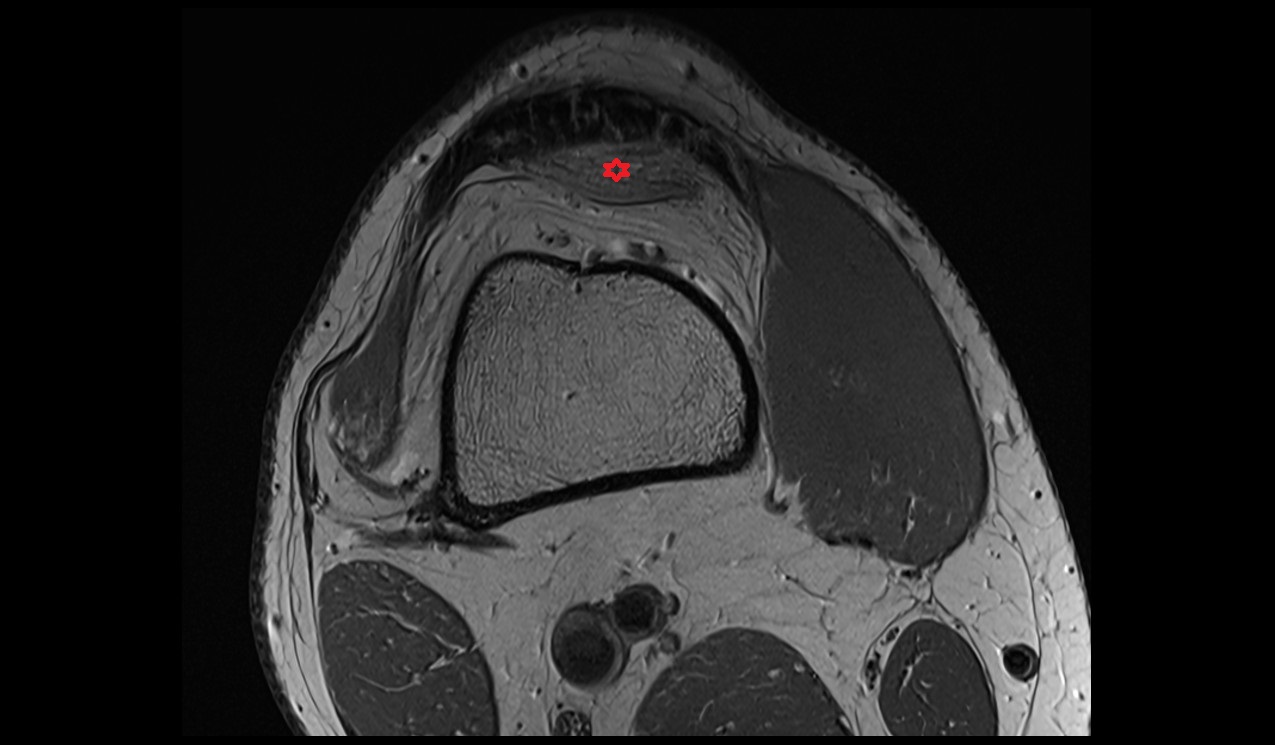

- Medial collateral ligament

- Lateral collateral ligament

- Medial patellofemoral ligament

- Lateral patellofemoral ligament

- Patella

- Patellar articular cartilage

- Infrapatellar fat pad

- Trochlear groove